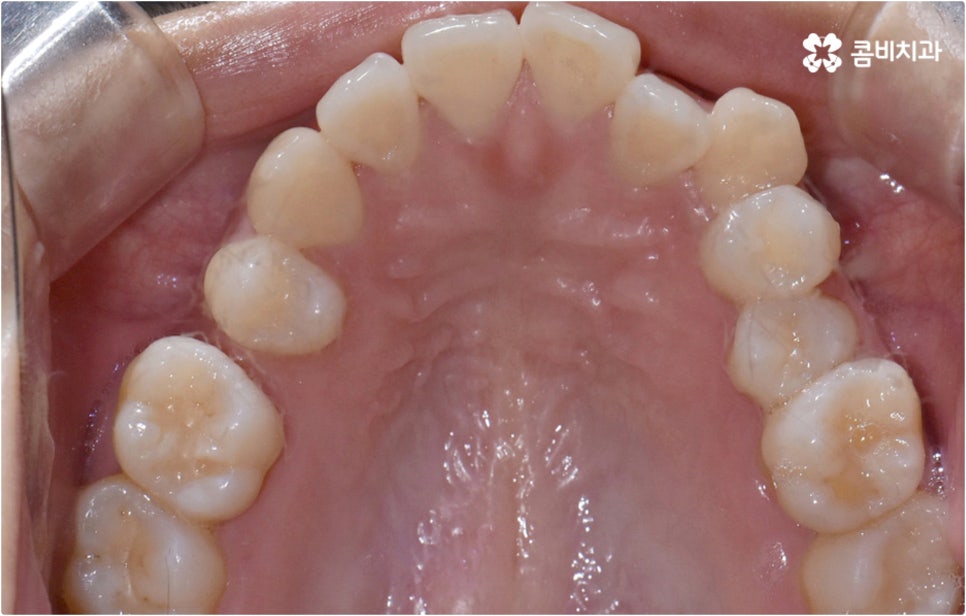

만약 정밀 검진을 해 보았는데 부정교합 정도가 심각하지 않고 턱관절 또는 구조적인 부분에 별다른 문제가 없는 상태에서 치아 사이가 약간 벌어지거나 각도가 앞으로 조금 뻗고 살짝 삐뚤어진 경우처럼 경미한 치열 이상 케이스라고 한다면 해당 부위만 브라켓을 부착하여 보다 빠르고 간편하게 이를 개선할 수 있는 부분 교정 치료나 투명교정을 진행해 볼 수 있어요. 환자분들에 따라 정확한 기간은 달라지겠지만 부분 교정이나 간단한 투명교정은 평균적으로 4~8개월 정도 소요되기 때문에 2년 넘게 걸릴 수도 있는 전체 교정 치료에 비해 기간 부담이 줄어들 수 있으며 대개 치아를 뽑지 않는 비발치 과정으로 진행되기 때문에 환자분들의 통증이나 두려움 또한 감소시킬 수 있습니다.

그러나 누구나 부분 교정이 가능한 것은 아니며 실제로 검진을 해 보면 부분 교정 보다 전체 교정이 필요하다고 판단되는 경우가 많아 내심 실망하실 수도 있는데요. 이때 만약 무리해서 환자분들 자신이 원하는 대로 부분 교정을 고집하게 되면 치아 이동 결과가 만족스러운 수준까지 이루어지기 어렵고 부정교합의 원인에 대한 구조적인 개선이 미흡하여 문제가 재발하기 쉬우니 노하우가 풍부한 담당 의료진의 판단을 심사숙고 해 보실 필요가 있어요. 무작정 따라야 한다는 것이 아니라 숙련된 의료진이 환자분들 치아의 위치와 각도 및 교합, 그리고 구조적인 원인 등을 세심하게 검진하고 꼼꼼하게 체크하여 삐뚤어진 치열을 보다 효과적으로 바로잡는데 전체 교정 치료가 필요한 상황이라고 결론 내린 것이니 만큼 그 필요성에 대해 스스로 이해할 수 있도록 충분한 상담을 받아 보시길 권유드리는 거예요.

이때 현재 상황을 정밀하게 보여주는 3D CT, 미래 결과를 예측해서 보여주는 모르페우스와 같은 디지털 장비를 통해 전체 플랜을 자세하게 설명해 주고 중간 과정 역시 꼼꼼하게 브리핑해 주는 의료진과 함께 교정 치료를 진행한다면 조금은 길고 힘들게 느껴질 수 있는 전체 교정 과정에 보다 적극적이고 긍정적인 마음으로 임할 수 있을 거예요. 또한 앞서 말씀드린 것처럼 불편함을 줄여줄 수 있는 다양한 교정 장치와 방법 등이 있으니 가능한 선택지 내에서 자신의 상황에 최적화된 장치를 이용해 보시면 여러모로 도움을 받으실 수 있습니다.

이와 같이 치아설측교정 과 콤비교정은 브라켓을 치아 안쪽으로 붙여서 치료하는 방식이기 때문에 굉장히 고난도의 복잡한 교정 치료라고 할 수 있습니다. 교정에 대한 높은 이해도와 해부학적으로 뛰어난 노하우, 풍부한 경험을 통해 축적한 세심한 기술력을 갖추고 있는 의료진에게 치료를 맡기는 것이 중요하며 정밀 디지털 검진 장비를 통한 정확한 검사 결과를 바탕으로 무리하지 않게 진행하실 필요가 있어요. 또한 양치질을 할 때 음식물 제거가 쉽지 않으므로 환자분들 본인이 평상시 신경써서 닦아주시는 것은 물론 꼼꼼한 케어시스템을 통해 주기적으로 관리해 주는 치과에서 교정 치료 및 사후 유지 관리까지 철저하게 받아보시길 권유드리고 있습니다.